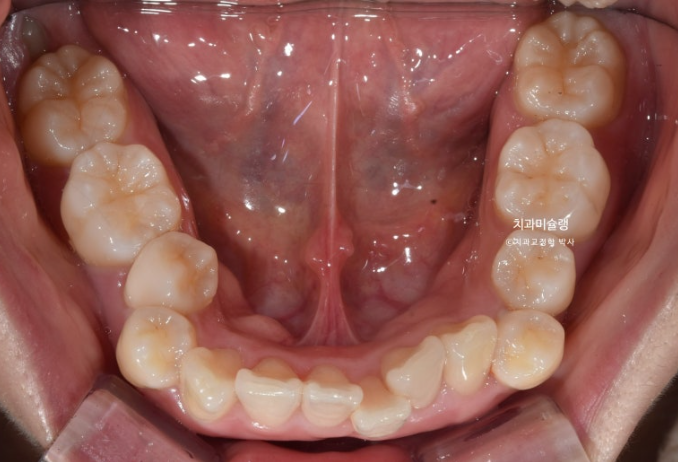

아래 치열은 덧니가 심한 상황입니다.

골격분석 결과 심한 상악골 전방 돌출을 동반한 골격성 2급 부정교합 입니다.

상악골 과잉에 의한 돌출은 돌출입 교정 중에서도 난이도가 높습니다.

상악과 하악의 골격 부조화가 심해 아래턱이 상대적으로 뒤로 밀려있는 상태여서 위 앞니 각도를 이상적으로 유지하기가 쉽지 않습니다.

입이 안 다물어질 정도의 윗니 돌출과 심한 아래 덧니를 해결하려면 작은어금니 4개 발치는 불가피합니다.